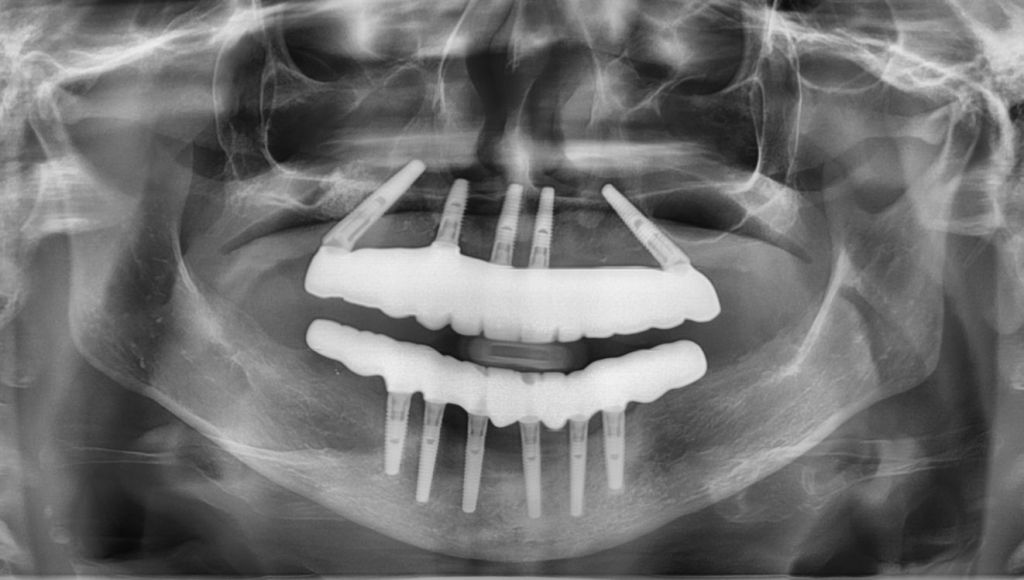

The answer is a resounding YES! It’s technically possible, but it’s also very easy to be exposed by radiographs or a CT scan. Doing so would have put that spy dentist at great risk. I would not wanna be that person.